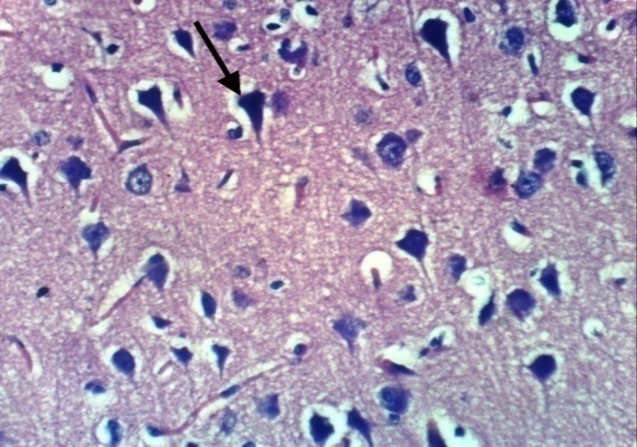

Microscopically, cerebral cortex of control, untreated rats revealed no histopathological changesas compared to normal control rats (Photomicrographs 1). Also, the cerabral cortex of treated rats with H. Pluvialis showed no histopathological changes(Photomicrographs 2,3) comparing to normal control rats. Meanwhile, cerebral cortex of rat treated with Al showed congestion of cerebral blood vessel (Photomicrograph 4), necrosis of neurons (Photomicrograph. 5) and multifocal cerebral haemorrhage (Photomicrograph 6). Examined sections from rats treated with rivastigmine revealed neuronophagia of sporadic necrotic neurons (Photomicrograph 7) and necrosis of some neurons (Photomicrographs 8). Some examined sections from rats treated with H. Pluvialis extract showed no histopathological changes (Photomicrograph 9), whereas, other sections revealed necrosis of neurons (Photomicrograph 10). In addition, the hippocampus of control, untreated rat revealed no histopathological changes (Photomicrographs 11 and 12). However, the hippocampus of rat treated with Al showed necrosis of pyramidal cells Photomicrograph. 13). Some examined sections from a rat treated with rivastigmine showed no histopathological changes (Photomicrograph14), whereas, other sections from this group revealed necrosis of some pyramidal cells (Photomicrograph 15).

| Photomicrograph 5: Cerebral cortex of rat treated with Al showing necrosis of neurons (H and E X 400) | Photomicrograph 6: Cerebral cortex of rat treated with Al showing multifocal cerebral haemorrhage (H and E X 400) |

Histopathological investigation of cerebellum and hippocampus of AD rats in the present results revealed necrosis of neurons and multifocal cerebral haemorrhage in addition to necrosis of pyramidal cells. While AD rats treated with neuronophagia of sporadic necrotic neurons and necrosis in the cerebellum as well as some necrotic pyramidal cells In accordance with the present results Salem et al. [1], showed severe congestion in the blood vessels with oedema in the meninges of AD-induced rats. While a micrograph of a brain section of AD-induced rats treated with rivastigmine showing no histopathological alteration in the hippocampus. These results are in agreement with the results of Bihaqia et al. [39], who showed the normal histological appearance of the brain cells treated with rivastigmine tartrate and revealed that rivastigmine reversed histopathological alterations caused by Al.

On the other hand, treatment of AD-induced rats with H. Pluvialis extract showed no histopathological changes in the cerebellum, whereas, other sections revealed necrosis of neurons. However no histopathological alteration was detected in the hippocampus of H. pluvialis extract treated AD rats, which may be contributed to, in AD induced rats ROS interact with nitric oxide (NO) to form peroxynitrite (ONOO−), a highly toxic compound. The bioavailability of endothelial NO is then reduced, and its vasoprotective effect is disrupted [40]. However, treatment with H. pluvialis containing antioxidant molecules, especially carotenoids, which play an important role in the control of the oxidative process. These antioxidant molecules (carotenoids) possess a strong antioxidant power due to their double-bonded structure, allowing the delocalization of impaired electrons, reducing oxidative damage and hence tissue architectures [2].